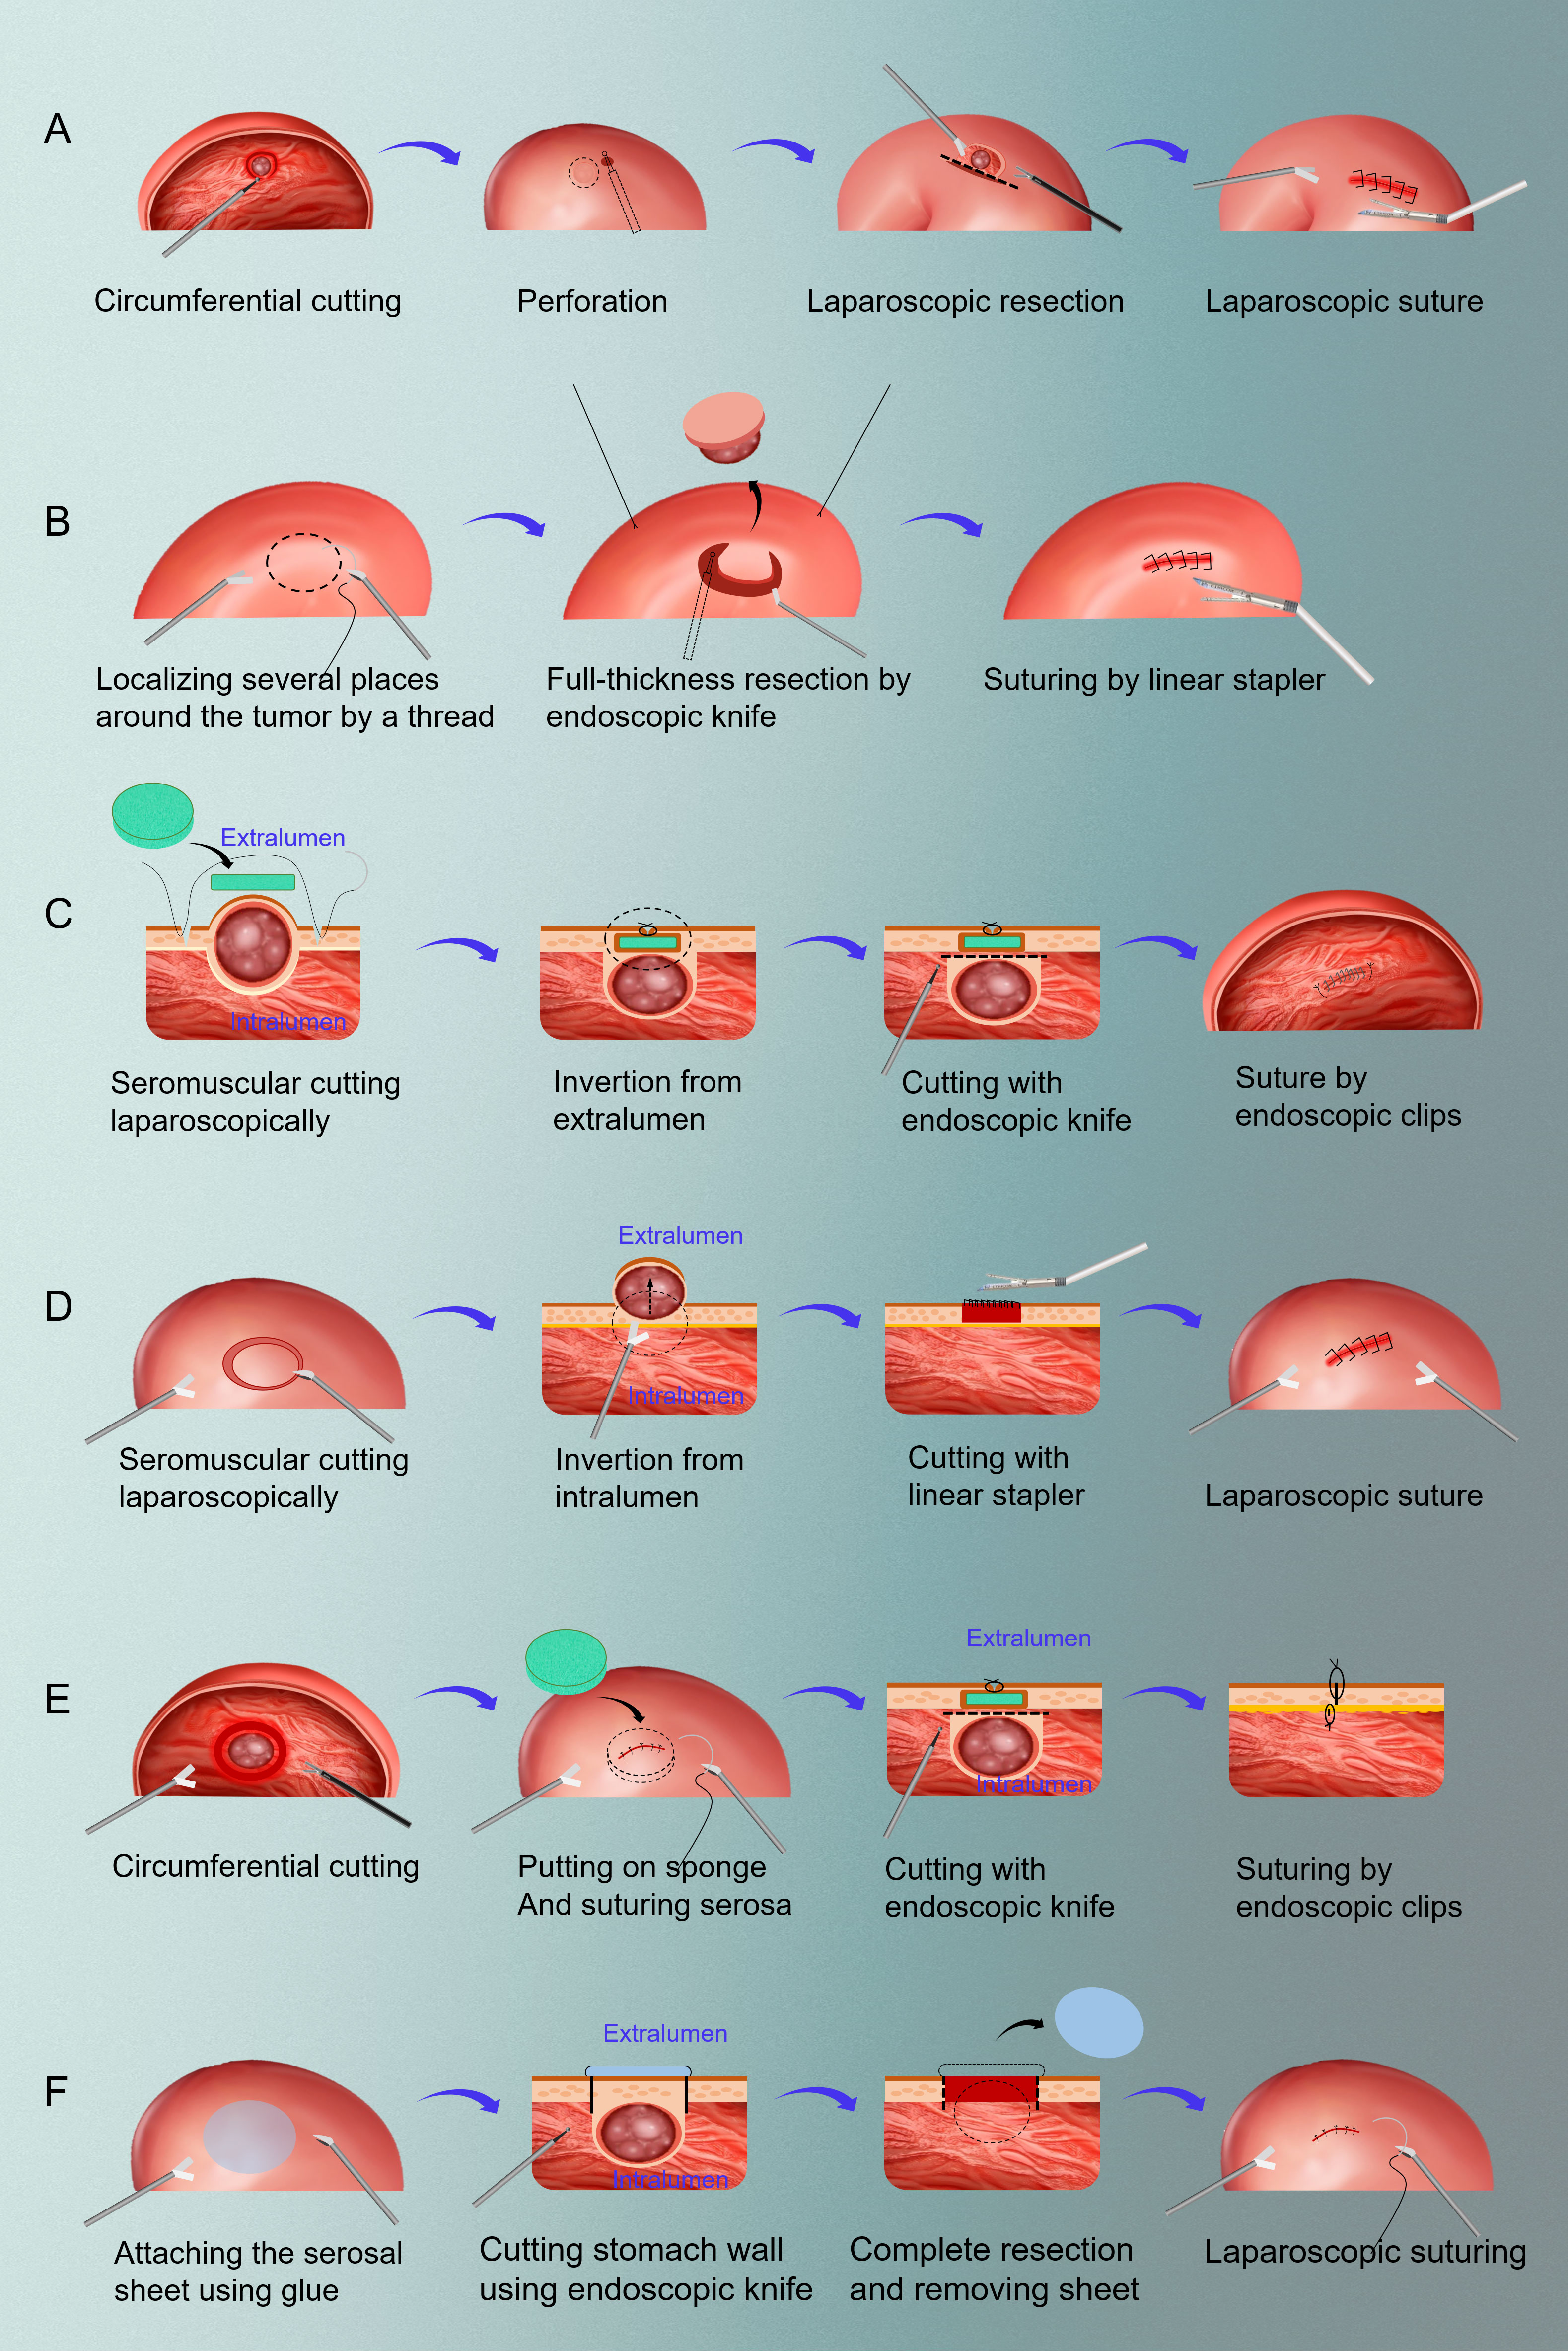

Amazon.co.jp: 子宮体癌・卵巣癌におけるStaging Laparotomy: en。改訂2版 子宮体癌・卵巣癌におけるStaging Laparotomy。Raising Awareness of Intraoperative Diagnostic Challenges to。中古品を購入し、自宅で裁断しました。裁断面は綺麗です。(写真2枚目)表紙カバーなどにヨレがあります。(写真3,4枚目)自宅で問題なくスキャンできました。ペット、喫煙なしです。※DVDなしです「子宮体癌・卵巣癌におけるStaging Laparotomy en bloc骨盤・傍大動脈リンパ節郭清術」田畑 務定価: ¥ 18000#田畑務 #田畑_務 #本 #自然/医療・薬学・健康。595_2020_2121_Fig1_HTML.png。小児歯科学クリニカルテキスト・ベーシックテキスト 第2版。【大型本】講談社 顎口腔外科診断治療大系。ゲノム 生命情報システムとしての理解。リンパ系局所解剖カラーアトラス